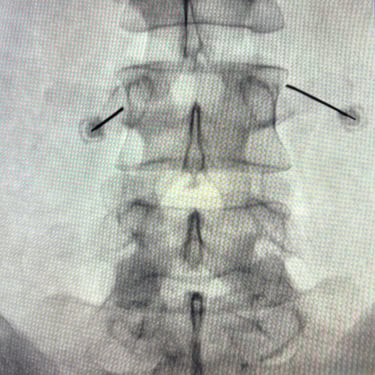

La discopatía lumbar y la espondiloartrosis forman parte del proceso degenerativo de la columna vertebral y pueden generar dolor lumbar persistente, irradiación hacia miembros inferiores y limitación funcional. Diversos estudios clínicos han demostrado que el bloqueo lumbar selectivo es una herramienta diagnóstica y terapéutica útil en estos pacientes. El procedimiento consiste en la infiltración guiada por fluoroscopía o ecografía de anestésicos locales y corticoides cerca de la raíz nerviosa o articulación facetaria comprometida. Esta técnica permite confirmar la fuente del dolor y disminuir la inflamación neural. En pacientes seleccionados, puede mejorar significativamente la calidad de vida y retrasar o evitar tratamientos quirúrgicos.